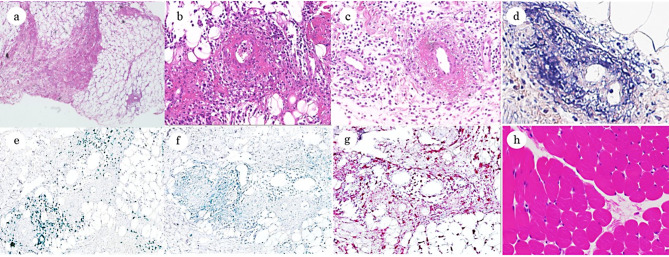

Case presentation: The patient developed a high fever and skin swelling with pain and erythema on the right side of his body following an abrasion injury on his right wrist at the age of 5 years, and was suspected of having streptococcal toxic shock-like syndrome, for which he received antimicrobials, immunoglobulin therapy, debridement, and plasma exchange. The same manifestations with similar magnetic resonance imaging (MRI) findings of high signal on short tau inversion recovery showing the spread of inflammation in the fat tissue and fascia was observed twice at the age of 6 years. Serological analyses for conventional autoantibodies, bone marrow aspiration, and whole-exome sequencing examination were non-remarkable. Prednisolone was effective in ameliorating the above putative autoinflammatory syndrome. The patient was admitted at the age of 10 years with similar clinical and MRI findings indicative of recurrence of the same disease. En bloc biopsy from the skin to the fascia showed thickening of collagen fibers, infiltration of inflammatory cells composed mainly of neutrophils and lymphocytes, and necrotizing vasculitis in the fat tissue and fascia. Immunohistochemical staining of the en bloc biopsy sections indicated infiltration of T lymphocytes and macrophages in the perivascular connective tissue and fibrinoid necrosis, supporting the diagnosis of FPS. Induction therapy with prednisolone resulted in a remission. IgG purified from the patient's serum reacted with pericellular basement membranes in the subcutaneous fat tissue by immunohistochemistry. The patient is currently taking famotidine to prevent relapses and is making good progress in his recovery.